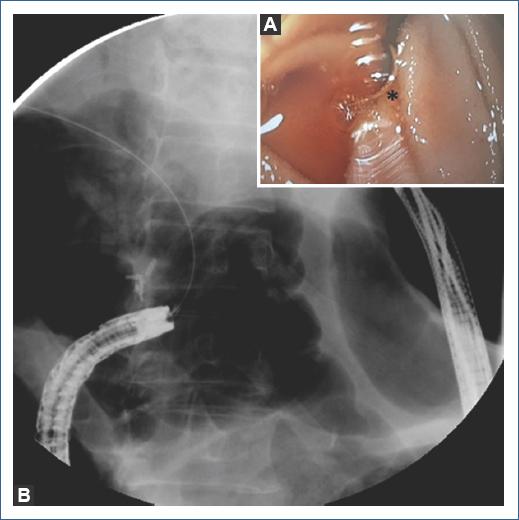

First, a colonoscope (190 Olympus Medical Systems, Tokyo Japan) was passed up to the choledochojejunostomy, which was found kinked and angulated. Therefore, the colonoscope was withdrawn and an enteroscope (EVIS EXERA II [SIF-Q180], Olympus Medical Systems, Tokyo Japan) was passed until the kinked choledochojejunostomy. Second, a hydrophilic Guidewire (0.035 mm Jagwire Revolution High Performance Guidewire, Boston Scientific Corp) was introduced percutaneously into the biliary tree under transabdominal ultrasound assistance to access the afferent limb (Fig. 1), and the guidewire was recovered with the enteroscope (Fig. 2). Third, the enteroscope holding the guidewire was withdrawn and interchanged into a stent-loaded colonoscope. Finally, the colonoscope holding the guidewire was introduced and an enteral uncovered self-expandable metal WallFlex Duodenal Stent, Boston Scientific Corp (22 mm × 60 mm) was successfully deployed at the site of the obstruction (Fig. 3). The schematic representation of the technique is described in figure 4. The patients evolution was satisfactory and was discharged 48 h after the procedure.

Figura 2 A: endoscopic view of the hydrophilic guidewire (asterix) emerging through the kinked choledochojejunostomy. B: hydrophilic guidewire retrieved with the endoscope.